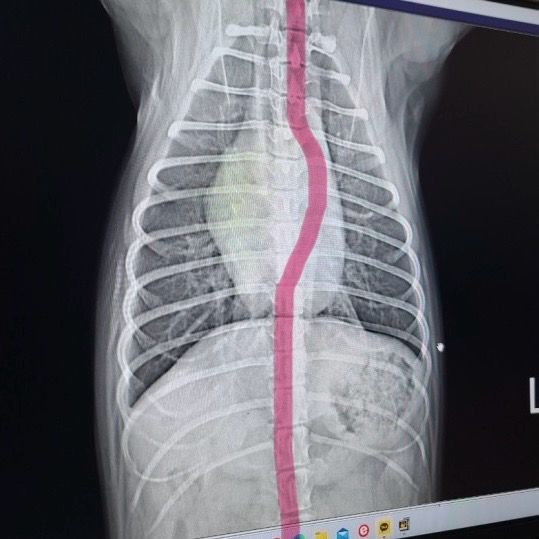

안녕하세요, 강아지 건강검진을 받았는데 엑스레이상 흉골이 휘어보인다해서요, 외부충격은 없었고 기침이나 등 다른 증상은 없습니다. 일년전 다른 병원에서 건강검진 때 엑스레이에선 휘어보이지않는데 엑스레이를 잘못찍으면 흉골이 휘어보일수있나요? 아니면 다른쪽에 문제가 있을 수 있는건가요.. 첨부한 사진은 실제 사진이 아니고 빨갛게 그린게 저희 강아지 엑스레이상 휘게 나온걸 보여드리고 싶어서 첨부했습니다. 정면 엑스레이에서 흉골이 사진 빨간 부분처럼 좀 휘게 나왔습니다.

1년전에 찍은 사진에도 휘어 있었는데 인지하지 못했을 가능성을 배제할 수 없습니다. 빨간 선 없는 사진을 봐야 실제 이 사진에서도 오해가 있는지 확인 가능합니다.